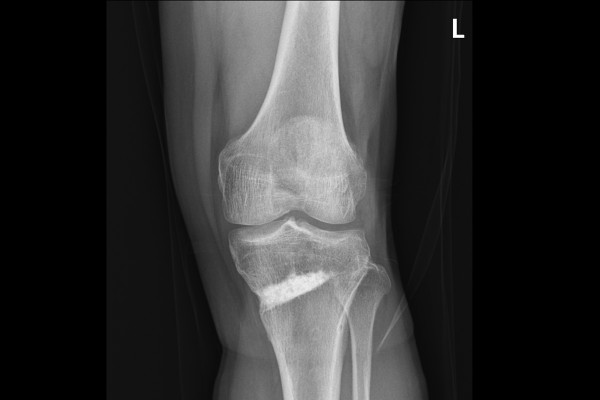

반면 반대쪽인 좌측 무릎에서는 관절 내 유리체가 확인되지 않고, 예전에 오다리 교정술을 받으신 흔적만이 보입니다.